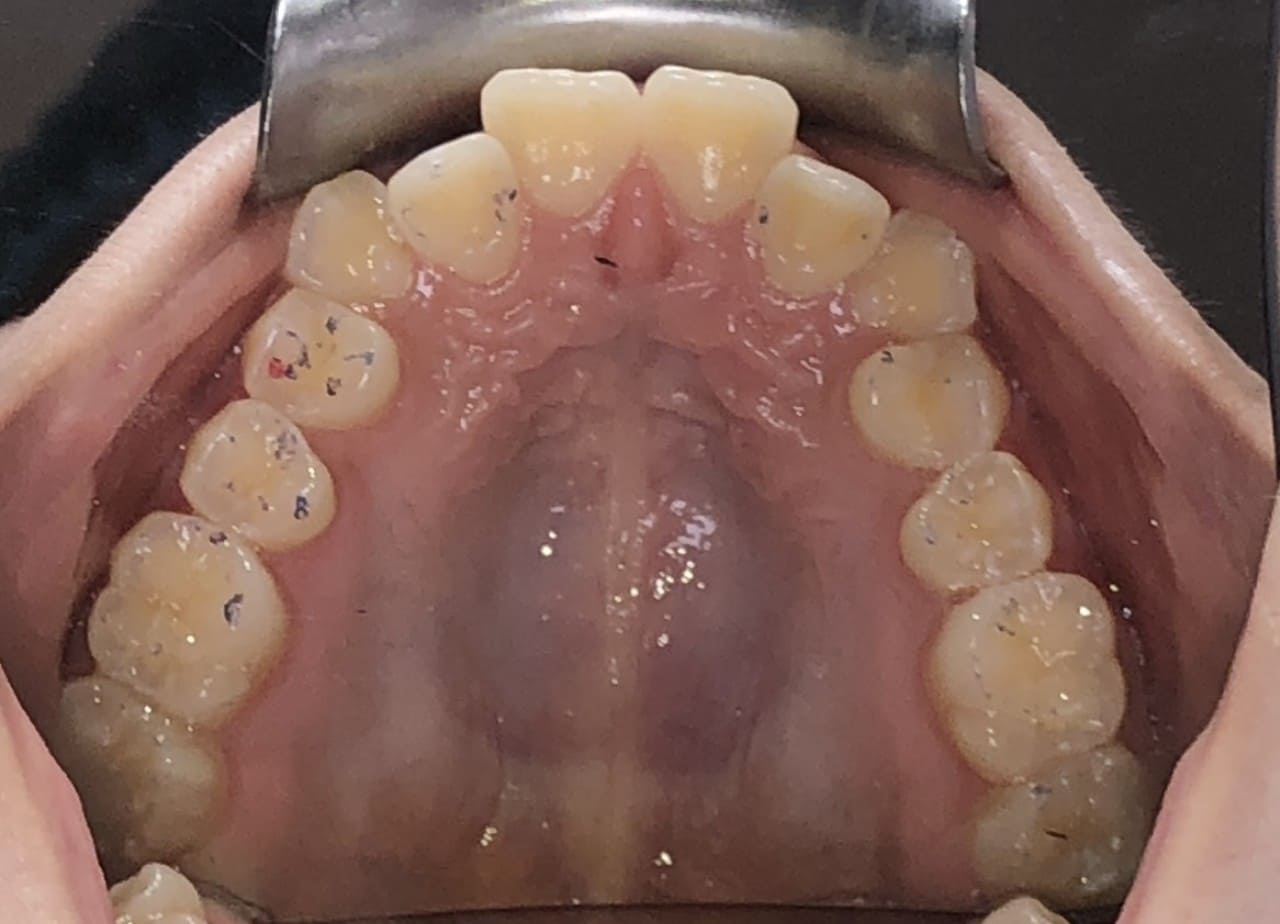

Initial